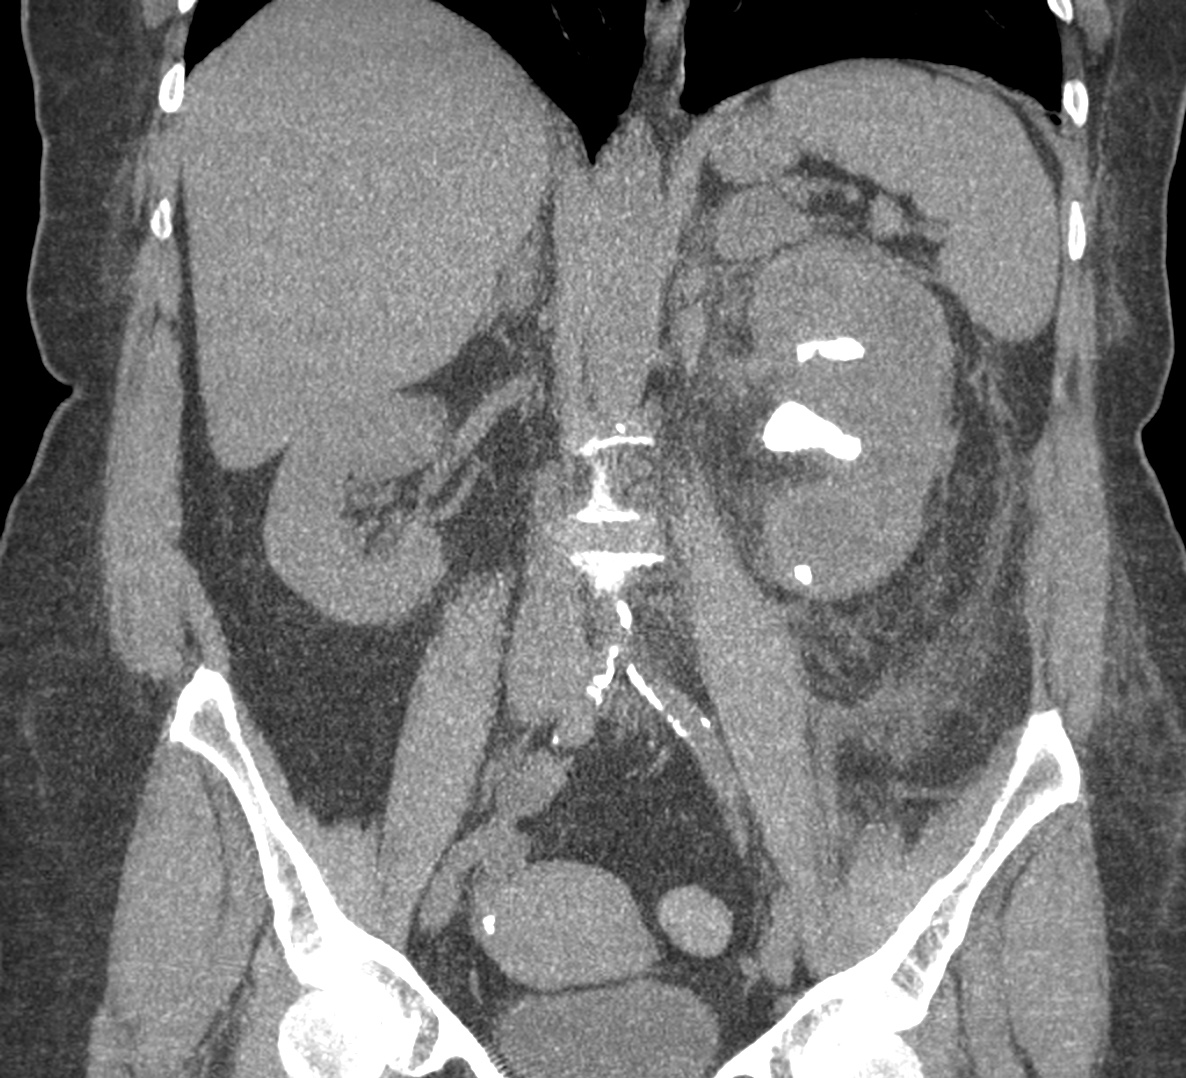

CASO 2: Paciente de 68 años con dolor en flanco izquierdo, fiebre y malestar general. A la exploración existe enrojecimiento de la piel con sensación de masa palpable y puño percusión muy positiva.

El paciente es alégrico al Iodo. Se realiza TC sin contraste para ampliar estudio.

Todos estos hallazgos están en relación con una Pielonefritis Xantunogranulomatosa que afecta al riñón derecho junto con una colección que ha fistulizado a región lumbar.

- Pielonefritis Xantunogranulomatosa.

- Es una forma infrecuente de pielonefritis crónica, de origen obstructivo, caracterizada por la formación de un absceso granulomatoso que puede extenderse al EPR-, severa destrucción renal y un cuadro clínico de fiebre, malestar general, dolor en el flanco y masa renal, a veces palpable.

- En placa simple podía verse un masa que renal con o sin borramiento de la línea del psoas. En ecografía, cálculos y aumento del tamaño renal en la forma difusa con múltiples áreas anecoicas correspondientes a las colecciones purulentas.

- Los hallazgos en TC pueden ser:

- Uni o bilateralidad de la lesión.

- Afección difusa o localizado.

- Litiasis de tipo coraliforme, calcificaciones intraparenquimatosas.

- Aumento difuso del tamaño renal.

- Áreas hipodensas o hipoecogénicas dentro de la lesión renal debidas a cálices dilatados, abscesos o áreas de necrosis parenquimatosa.

- Pobre o nula eliminación del medio de contraste en el riñón afectado.

- Compromiso inflamatorio que excede los límites del riñón y genera colecciones periféricas o extensión hacia vísceras vecinas.